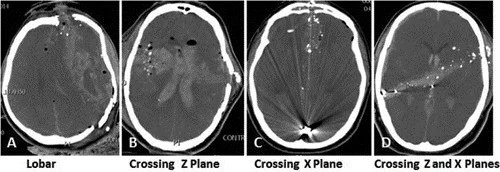

Head Injury Caused By Gunshot Gunshot wound to the head when caused by a bullet that is travelling at high velocity and force results in two types of injuries of the skull bone. The strike of smaller bullet over the skull causes penetrating cone shape inlet of the bone and larger bullet causes bullet entry surrounded by fracture of skull bone.

The brain damage depends on following factors

- The distance bullet travels through brain tissue

- The direction of passage of bullet

- The distance of the shooting range

- Projectile path prior to bullet strike to skull bone and

- Type of bullet fired.